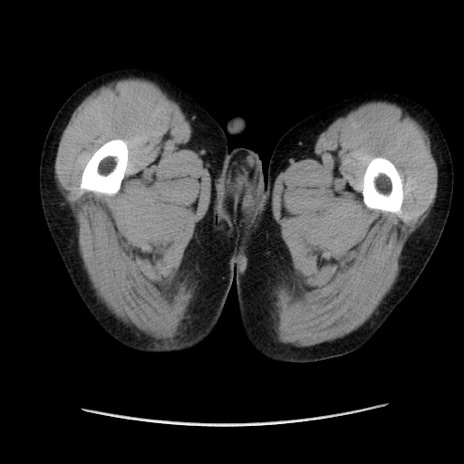

症例37(横断像)

【症例】40歳代 男性

【主訴】腹痛

【現病歴】4時間ほど前に電車に乗車中に臍部上より腹痛出現。徐々に増悪し起立困難となり、救急外来受診。生ものは数日食べていない。今朝お雑煮を食べた。

【身体所見】BT 36.8℃、BP 117/84mmHg、HR 91/min、SpO2 97%、苦悶様、腹部:臍上部広範囲圧痛あり、反跳痛±

【データ】WBC 8100、CRP 0.03